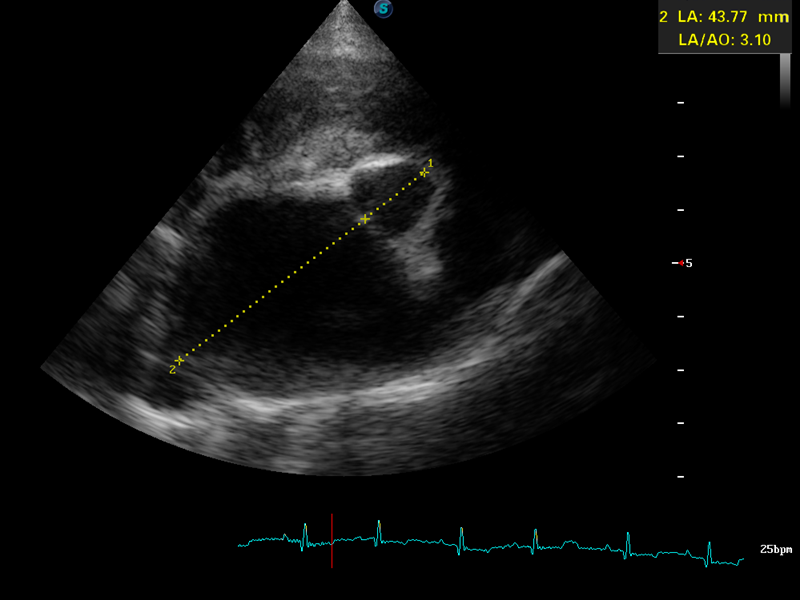

Caroline is an experienced first opinion vet, with a passion for ultrasound. She has supported CelticSMR customers for over 5 years with training in ultrasound and loves nothing more than sharing her expertise with vets to enhance their imaging and develop a standardized, repeatable technique for a complete abdominal ultrasound examination. Caroline loves teaching and says ‘I can help you learn a simple approach to your ultrasound machine to perfect image optimisation. As an experienced trainer, I know how to structure your training day to enhance skill acquisition. I love witnessing the transformation in confidence when it all falls into place!’. Merlin, her dog, is an integral part of her team, being a perfect size for abdominal and cardiac scanning.